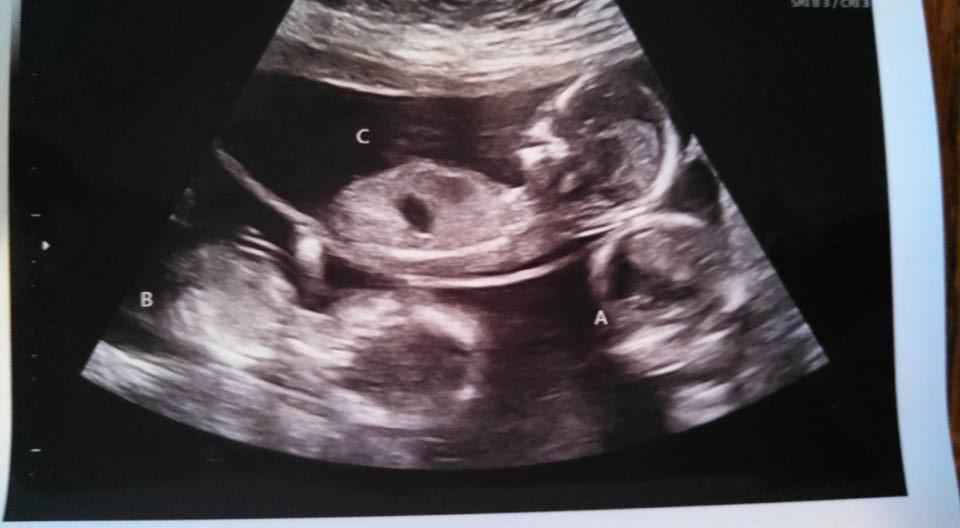

Triplets at 14w1d

Triplets due 6/29/16 also from an IUI!